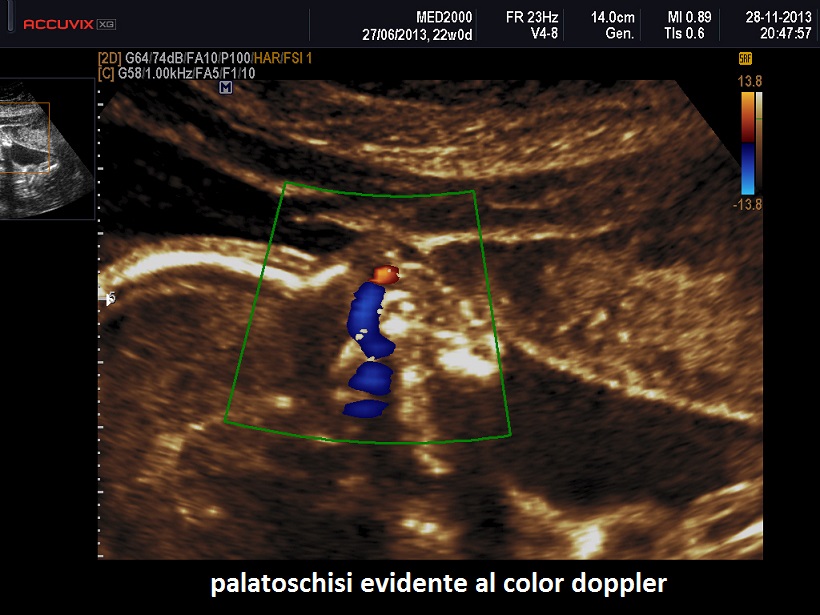

All'ecografia prenatale si riscontra ipoplasia toracica (torace stretto e coste corte), rizomelia lieve-moderata e frequentemente  displasia renale policistica.

Meno frequentemente è presente polidattilia postassiale; se e’ presente coinvolge mani e piedi.